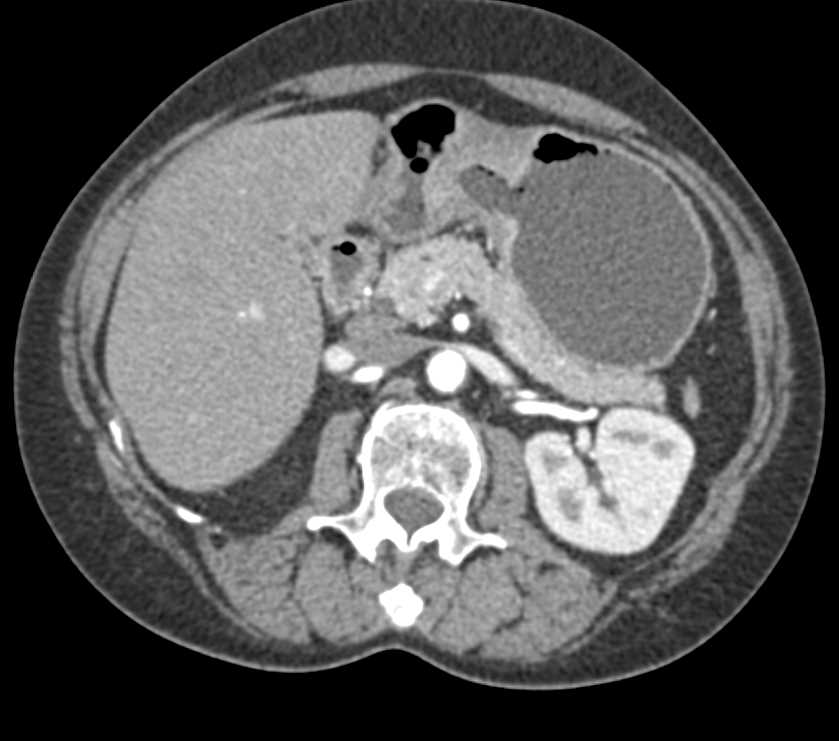

Infiltrating Gastric Cancer